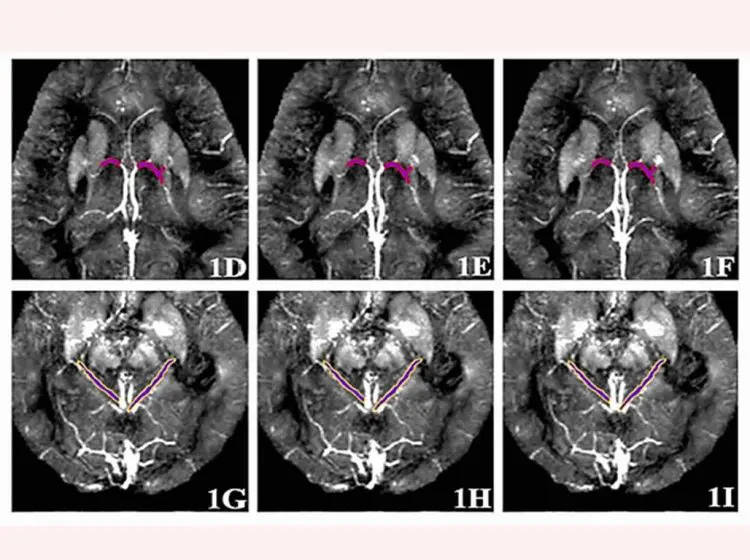

Новый метод от Пермского Политеха использует комбинацию магнитно-резонансной томографии (МРТ) и алгоритмов машинного обучения для исследования венозной сети обоих полушарий мозга.

Диагностика включает введение контрастного вещества на основе гадолиния, сканирование мозга и измерение магнитной восприимчивости в шести ключевых мозговых венах. Как пояснил Леонид Валерьевич Кожемякин, кандидат технических наук, начальник отдела инноваций Пермского Политеха, эти параметры дают ценную информацию о состоянии сосудов и уровне кислорода, изменения которых сигнализируют о развитии болезни Альцгеймера.

На следующем этапе полученные данные обрабатываются специально разработанной в Пермском Политехе программой, использующей алгоритмы машинного обучения («дерево решений»). Программа анализирует значения магнитной восприимчивости и выдает заключение: «CON» (здоров) или «AD» (болезнь Альцгеймера).